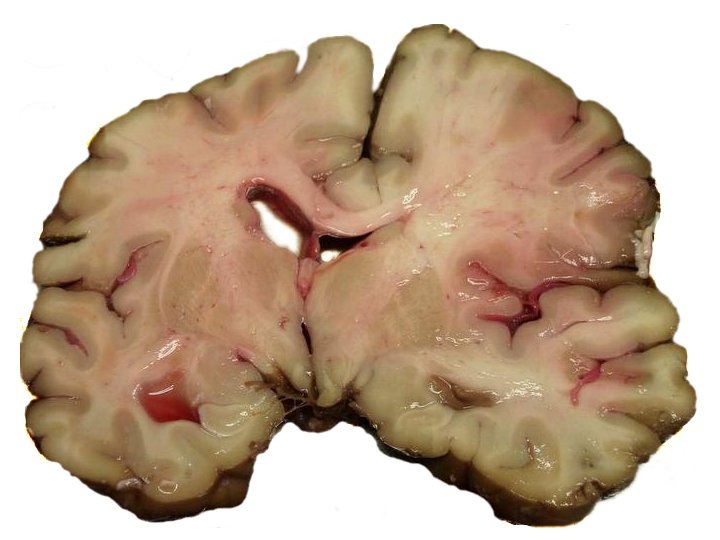

Чтобы понять профилактику, нужно понять суть проблемы. Простыми словами, инсульт — это острое нарушение кровоснабжения головного мозга. Клетки мозга очень чувствительны к нехватке кислорода и питательных веществ, которые доставляет кровь. Без этого снабжения они начинают быстро гибнуть.

Существует два принципиально разных механизма этой катастрофы:

1. Ишемический инсульт (≈80% случаев)

Представьте себе трубу, по которой течет вода. Если она засорилась, вода перестанет поступать дальше. То же происходит и с сосудом в мозге. Он закупоривается тромбом (сгустком крови) или атеросклеротической бляшкой. Кровоток прекращается, и участок мозга, который этот сосуд питал, начинает отмирать от кислородного голодания. Этот тип инсульта чаще происходит ночью или под утро.

2. Геморрагический инсульт (≈20% случаев)

Теперь представьте, что старая, изношенная труба лопнула под напором воды. В мозге происходит то же самое: ослабленная стенка сосуда (часто из-за высокого давления) не выдерживает и разрывается. Кровь изливается в ткани мозга, образуя гематому, которая сдавливает и повреждает нервные клетки. Этот тип инсульта обычно случается днем, на фоне физической или эмоциональной нагрузки, и часто протекает тяжелее.